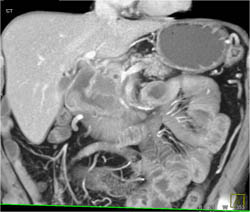

Tail of Pancreas Tumor Encases the Splenic Vein